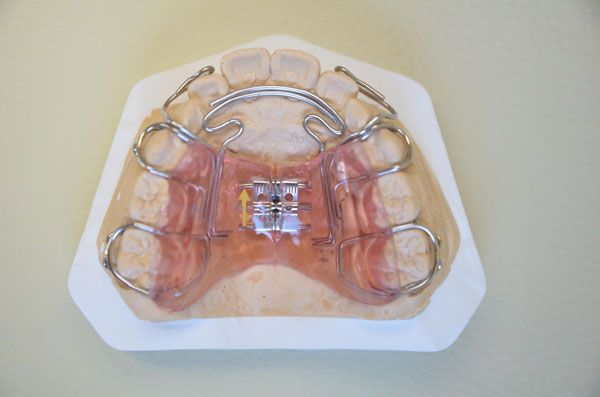

しょう(床)矯正装置を両手で上手にはめています。いい加減にはめたり、噛んで押し込もうとすると、針金が折れてしまいます。

このような取り外しの装置を上下にはめて、成長の誘導をしていきました。これ以外にも、いろいろな形や機能の装置を6個使いました。